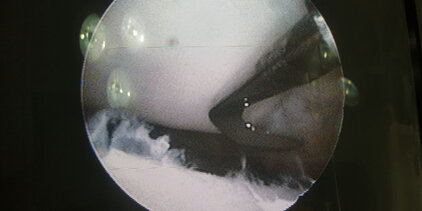

Arthrotomie/Arthroskopie

Minimal Invasive Diagnostik und Behandlung von Gelenkserkrankungen der großen Gelenke Schulter, Ellenbogen und Knie. Insbesondere Knorpel- und Knochenschäden in Schulter und Ellenbogen (OCD Osteochondrosis dissecans, FPC Frakturierter Processus coronoideus, IPA Isolierter Processus anconaeus), chronische Sehnenentzündungen der Bicepssehne im Schultergelenk und Band-/Meniskusverletzungen im Kniegelenk.